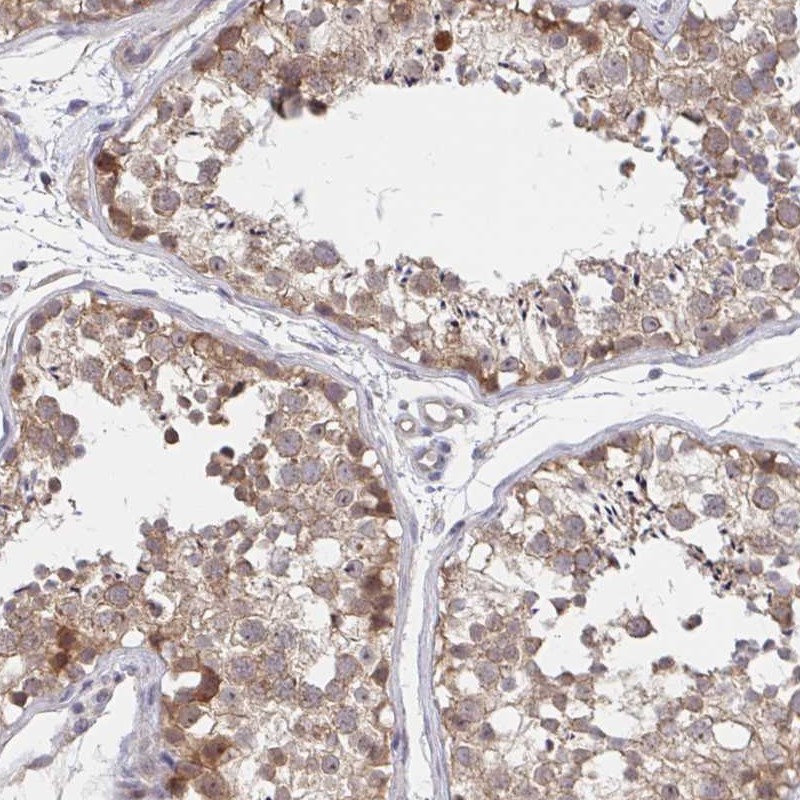

Immunohistochemical staining of human testis shows moderate cytoplasmic positivity in cells in seminiferus ducts.